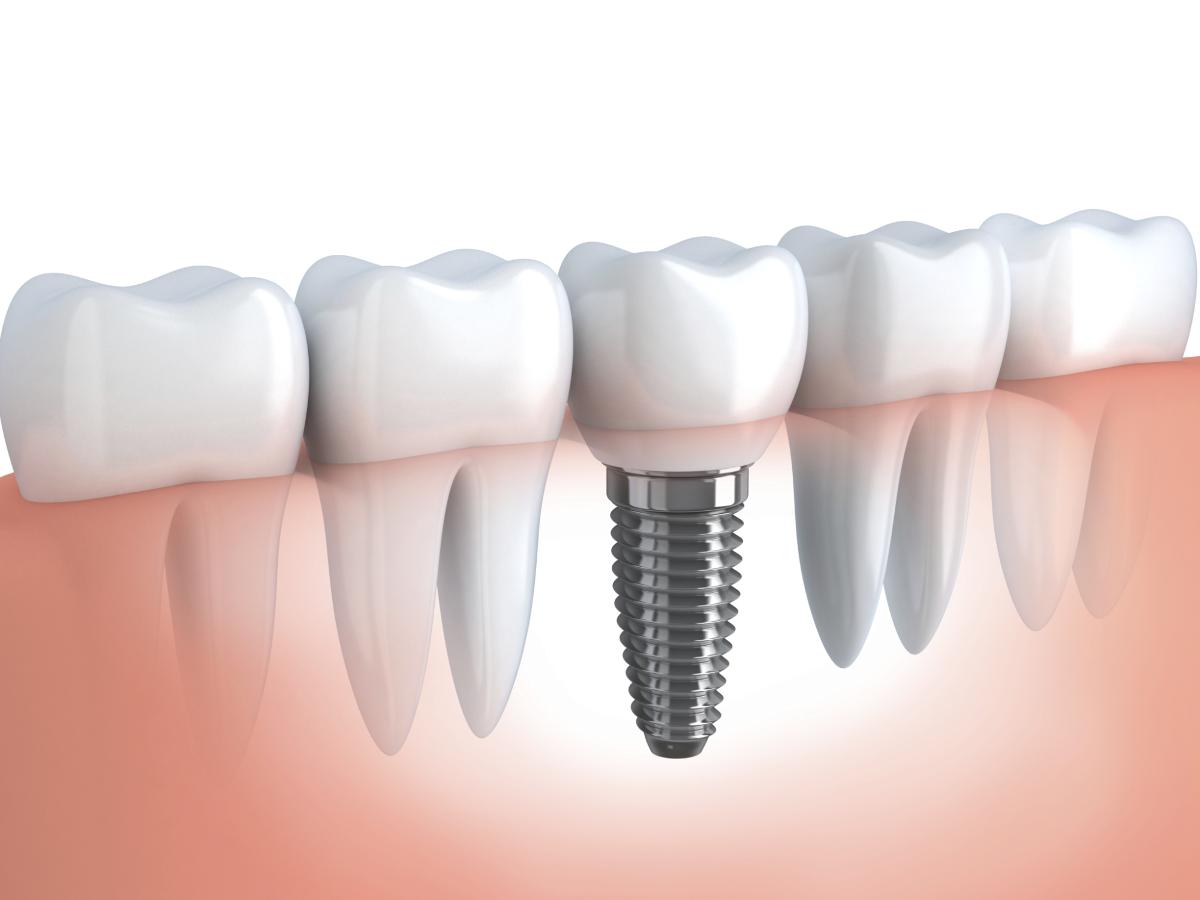

Виды имплантации зубов

В этой статье мы расскажем Вам про: классическую, базальную, а также экспресс имплантацию зубов.

Когда в зубном ряду по той или иной причины появляется пустое место (удален зуб), то следует заместить пустое место, потому что соседние зубы будут стараться закрыть дефект и мы получим кривой зубной ряд.